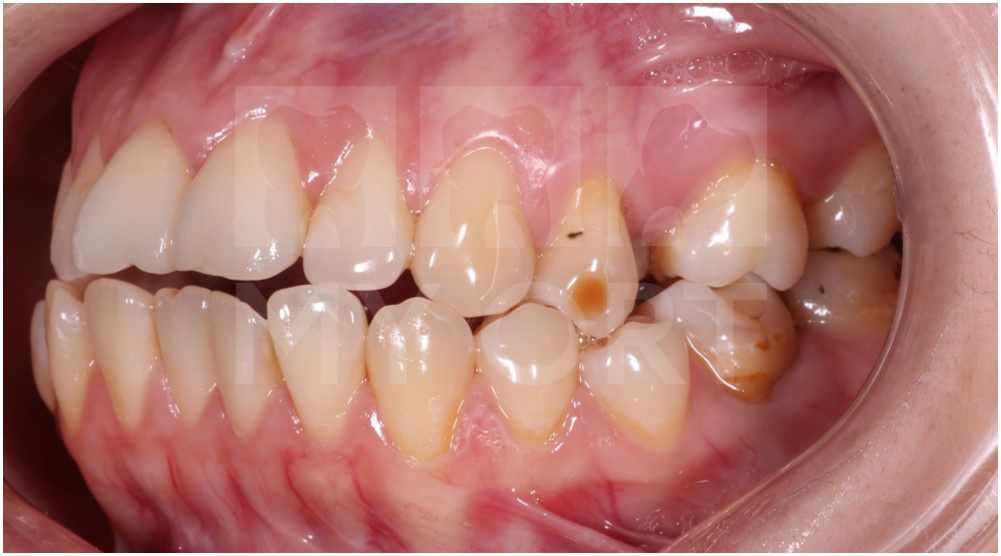

Исходная ситуация. Жалобы пациентки

Девушка 31 год.

Первая консультация девушки была у врача-хирурга по поводу имплантации в области отсутствующих зубов (4 и 5 зуб на верхней челюсти отсутствуют). После осмотра хирург направил ее ко мне (ортодонту) для исправления прикуса и создания условий под имплантацию и протезирование.